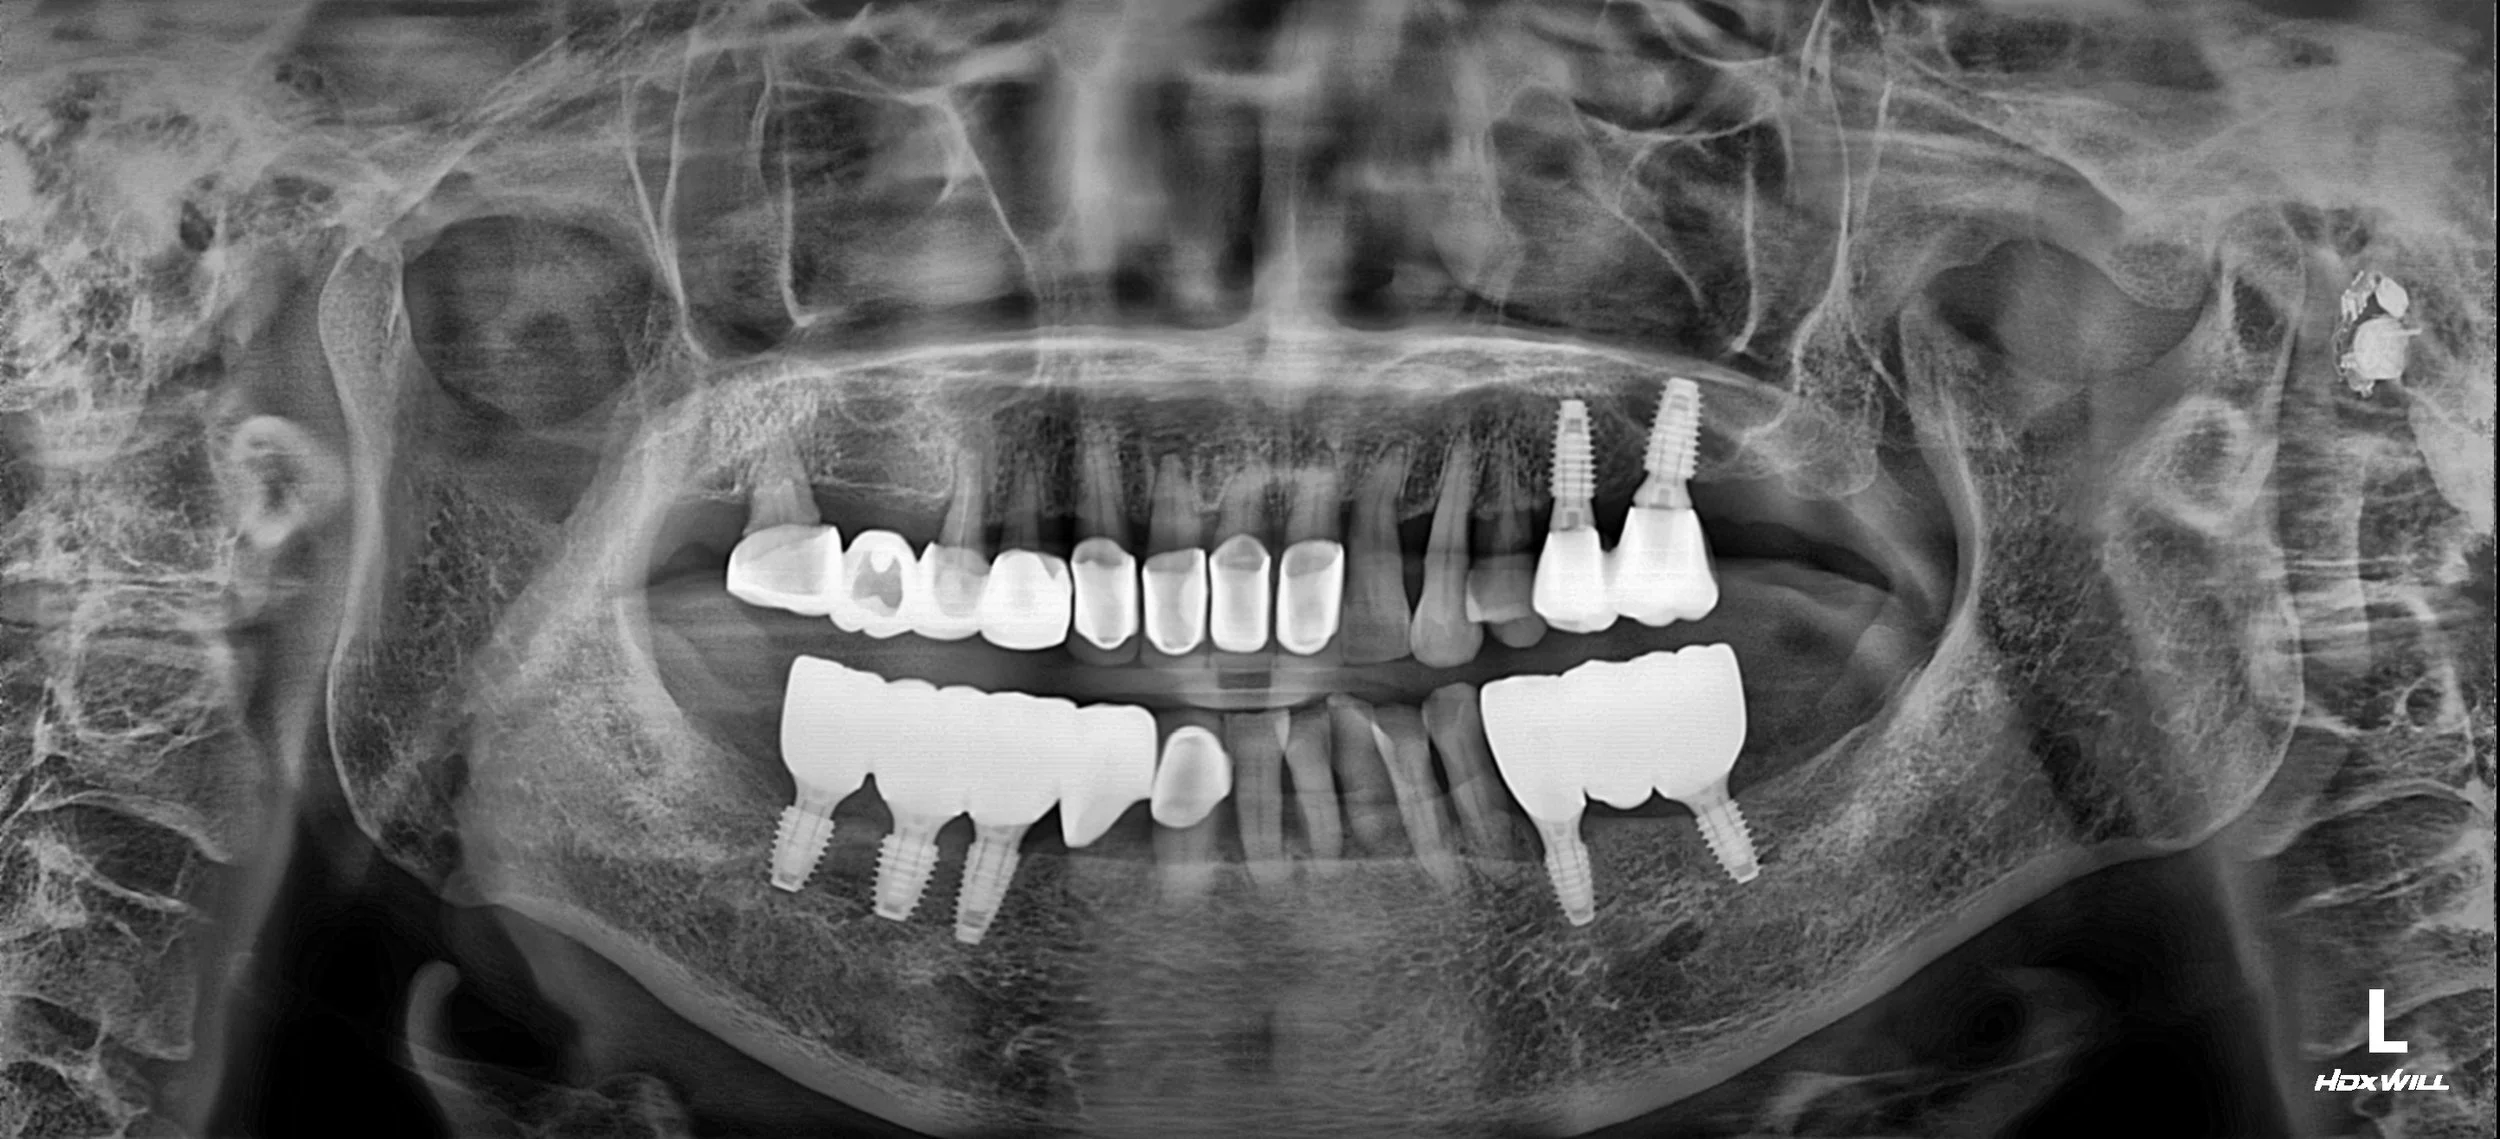

2. Surgical Phase: Dental implants were placed in the posterior regions of both arches. This was the most critical step to provide the "posterior stops" needed to stop the unilateral chewing pattern and redistribute occlusal forces evenly.

3. Prosthetic Realignment: Once the implants were integrated, the focus shifted to the anterior teeth. By coordinating the anterior crowns with the new posterior height, we were able to harmonize the occlusal plane and significantly improve the patient's facial symmetry.

4. Final Delivery: High-precision zirconia crowns and implant-supported bridges were delivered. The final result not only restored the ability to eat comfortably on both sides but also provided a naturally rejuvenated aesthetic appearance.